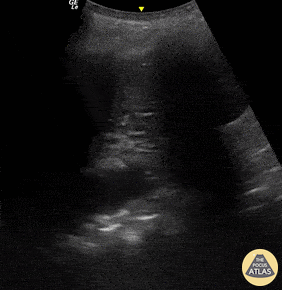

Pictured here are dynamic air bronchograms in a patient with bacterial pneumonia. Image was acquired using convex probe on the left PLAPS. Renato Melo, PocusJedi co-founder, Emergency Physician HC MarĂ­lia-SP, Brazil. @Renato_Melo_